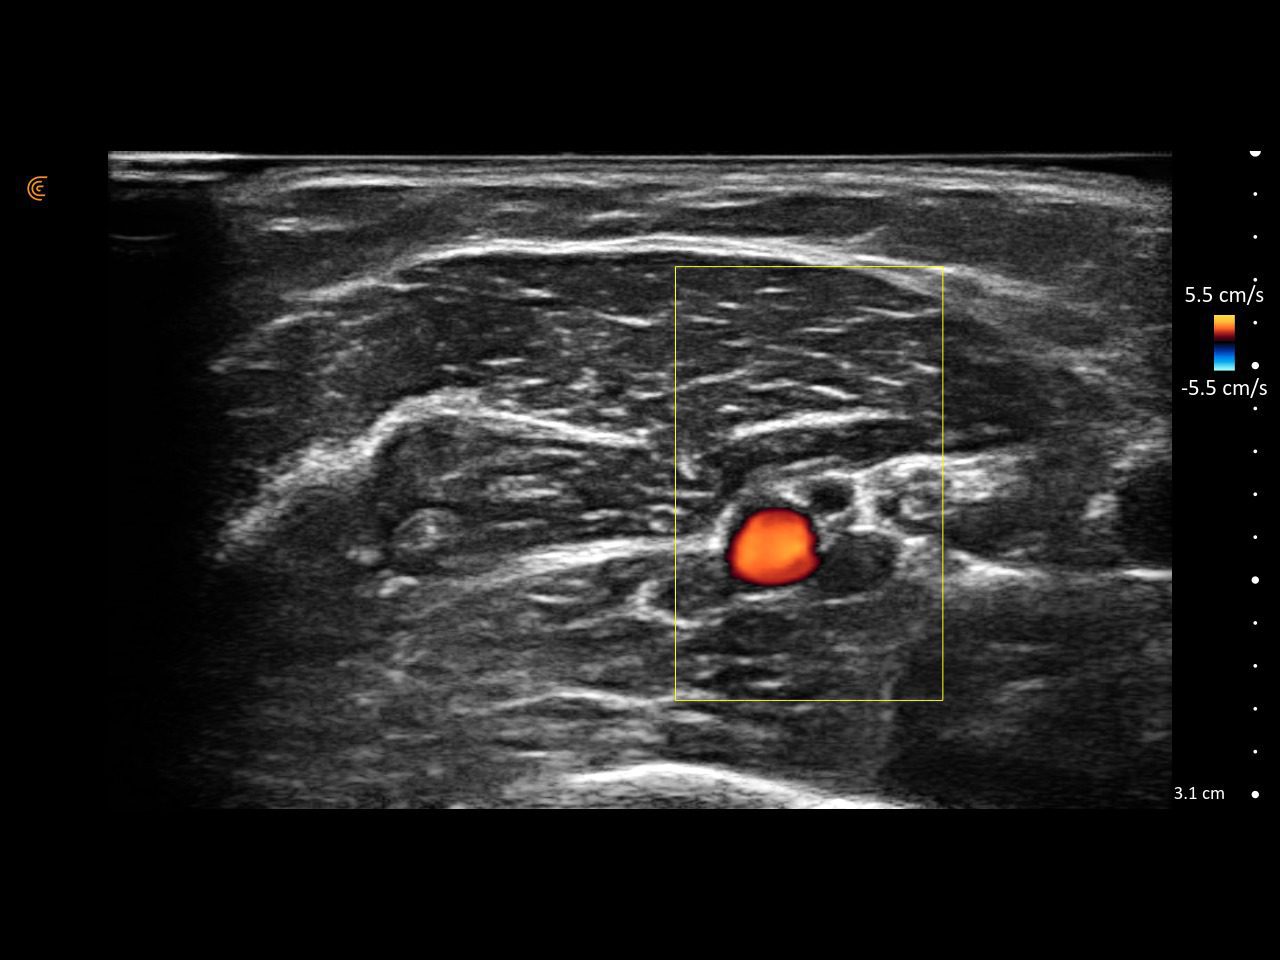

Visualize targets in real time for precise nerve blocks and corticosteroid injections—reducing injectate volumes and boosting safety, confidence, and patient outcomes.

Assess synovitis, enthesitis, and monitor treatment efficacy with high-resolution ultrasound, enabling precise, real-time joint and soft tissue evaluation, accurate needle guidance, and improved confidence in clinical decision-making.

From pre-op to PACU, guide safe, accurate blocks and pain interventions without disrupting workflow or sterility.